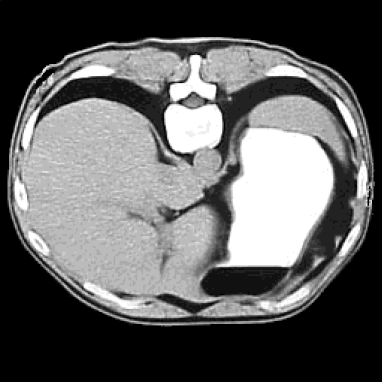

To simulate the internal data , we use an abdominal human CT image rescaled to a realistic range of tissue conductivity, with values varying from 1 to 1.8 S/m The scaled conductivity distribution, on a uniform grid , is shown in Figure 1.

We use in all the numerical experiments with the alternating Bregman algorithm. In our first experiment we choose the almost two-to-one boundary voltage . The results obtained by applying the split Bregman algorithm with iterations are shown in Figure 2. A larger image of the conductivity reconstructed using the alternating split Bregman algorithm with is shown in Figure 3. This image may be compared with the original image in Figure 1.